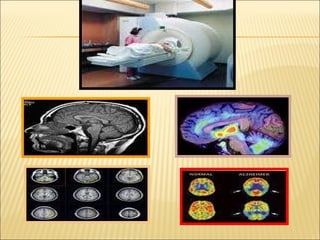

Bases biológicas de la Conducta Humana BIOPSICOLOGÍA: Enfoque biológico al estudio de la Psicología. Investiga las bases biológicas de la conducta y los procesos bioquímicos que acontecen  en nuestro organismo. Trabajo que se  centra en el Sistema Nervioso (SN) el cual contiene estructuras y células especializadas a su servicio.

Bases biológicas dela Conducta Humana BIOPSICOLOGÍA: Enfoque biológico al estudio de la Psicología. Investiga las bases biológicas de la conducta y los procesos bioquímicos que acontecen en nuestro organismo. Trabajo que se centra en el Sistema Nervioso (SN) el cual contiene estructuras y células especializadas a su servicio.